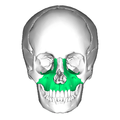

Side view. Maxilla visible at bottom left, in green.